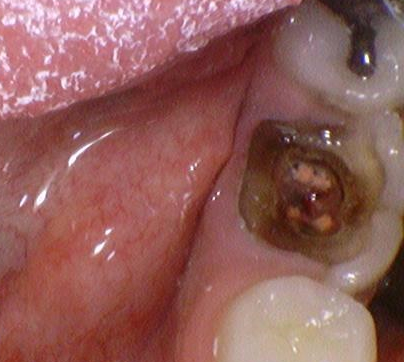

신경치료 후 크라운등 그 후 후속 치료를 하지 않아 치아머리가 거의 다 부서진 상태